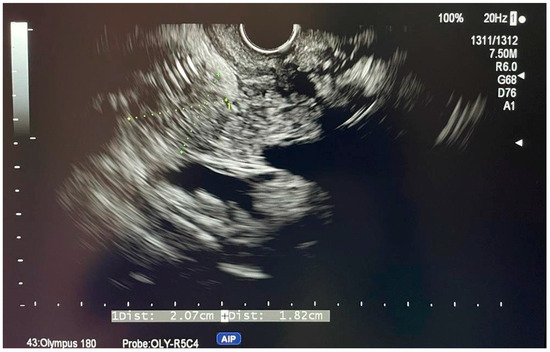

6.4.1. Endoscopic Ultrasound (EUS)

7.1.3. EUS-Guided Biliary Drainage (EUS-BD)